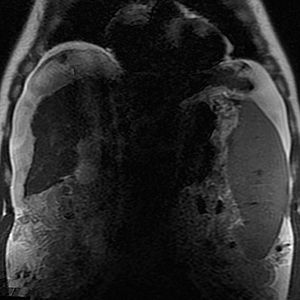

The term dielectric effect refers to the interaction of matter with the electrical (E) component of an electromagnetic field. Abnormal bright and dark areas due to B1 field inhomogeneity are frequently noted at very high fields (3T and above). Although the nature of these artifacts is not entirely clear, these are commonly referred to as dielectric artifacts.